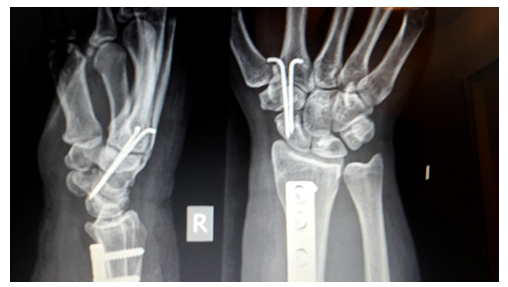

MRT-Kontrollen nach 7,5 Wochen und 3 Monate post OP im MVZ Bad Neustadt: Keine Besserung, aber auch kein Fortschreiten. Die Ärztin sagte mir bei der zweiten Kontrolle, die 2 Drähte (von der temporären STT-Transfixation) sollten noch bleiben, dann schickte sie einen abgeänderten Brief nach Rücksprache mit Dr. Kalb, dass sie doch schon raus könnten. Da war ich erstmal verwirrt und hab mal wieder meinen Cousin um Rat gefragt. Er hat sich noch mit einem Kollegen besprochen und wir entschieden, die Drähte vorerst zu belassen und zu hoffen, dass sich das Mondbein doch noch erholt. Das passierte leider nicht. Nach genau 6 Monaten (16.12.2016) wurden die beiden Drähte ambulant von meinem Cousin entfernt und noch einmal denerviert. Der Arm wurde nur über die Vene betäubt, das hat gut funktioniert, ich hatte nur wie bei mir scheinbar üblich "Kreislauf".

Mitte Dezember 2017 Routine-MRT-Kontrolle: Lunatum stabil schlecht, neu dazu deutliche STT-Arthrose (ich vermute durch die temporäre STT-Transfixation, die Drähte wurden nämlich mehrfach rein- und rausgeschoben bis sie endlich saßen) und eine mäßige Rhizarthrose (auf der anderen Seite habe ich auch eine, da sehe ich keinen Zusammenhang mit der LM). Weil ich nicht wieder ganz nach Neustadt fahren wollte, bin ich zu einem anderen Handchirurgen (Dr. M.N. in L.) gegangen, von dem mir Mitpatienten (mit anderen Diagnosen) in der Reha erzählt hatten. Er überlegte, einen Spacer an die Stelle des Lunatum zu setzen und eine STT-Arthrodese zu machen, wenn es weiter fortschreite, nach 6 Monaten sollte ich ein Röntgen machen lassen. Als ich einen Bericht anforderte, stand dann darin aber MRT-Kontrolle nach 6 Monaten, ggf. wolle man einen gefäßgestielten Knochenspan aus dem Radius einsetzen oder die o.g. OP. Interessant, das aus dem Brief zu erfahren! Ich machte also MRT- und Wiedervorstellungstermin bei ihm nach 6 Monaten aus.

Dr. Kalb hatte (scheinbar?) keinen wirklichen Favoriten und überließ mir die Wahl. Ich wählte Nr. 2, also das, was ich vorher nicht wollte, aber was mir nach allem Abwägen als Chance erschien. Die OP würde in einer Plexusanästhesie gemacht, 3 Nächte stationär, 6 Wochen Gips. Die Drähte könnten wie auch meine alte Platte am Radius drinbleiben. Falls die OP in seltensten Fällen nicht gut funktioniere, würde man es bald merken. Was mich besonders erleichterte, war, dass er sagte, die OP müsse solange ich mit den Schmerzen noch zurechtkomme und nichts Unvorhergesehenes passiere, nicht zwangsläufig zeitnah stattfinden und ich könne bis April (neuer Krankengeldanspruch) warten. Selbst wenn es etwas weiter fortschreite, könne man den Eingriff immer noch durchführen. Nun habe ich also 8 Monate Zeit, mich darauf einzustellen, dass meine inzwischen wieder fast normale Beweglichkeit nie wieder die alte sein wird.